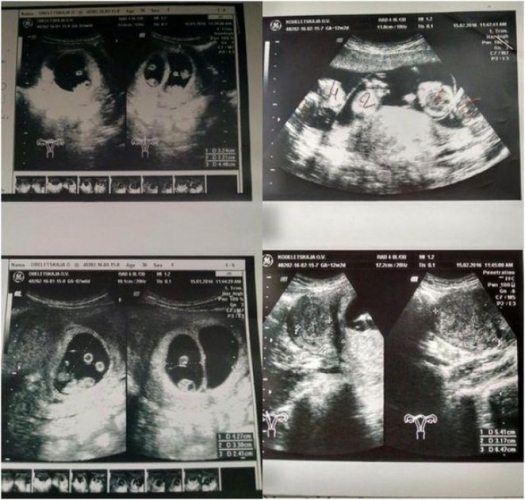

الايدا، ايەل كەزەكتى تەكسەرىستەن ءوتۋ ءۇشىن پەرزەنتحاناعا بارعاندا، دارىگەرلەر وعان ەستەن تاندىرارلىق جاڭالىق ايتتى.

«ءبارى ويداعىداي ءوتىپ كەلە جاتتى. ءبىراق، دارىگەر ەكرانعا قاراي بەرگەندە، ءتۇرى بوزارىپ سالا بەردى. مەنىڭ دە ۇرەيىم ۇشتى. جاتىرىمداعى بالا سانىن داۋىستاپ ساناپ جاتىپ، بۇنداي اناعا تەڭىز جاعاسىنان ءۇي سىيعا تارتۋ كەرەك»، - دەپ باسىن شايقادى.

ايتەۋىر، دارىگەر تەكسەرۋ ناتيجەسىمەن ءبولىستى: جاتىرىمدا بەس بالا بار ەكەن. بەس ءسابيدىڭ دۇنيەگە كەلۋى – وتە سيرەك كەزدەسەتىن جاعداي. دارىگەرلەر تاڭداي قاقتىردى، وكسانانىڭ ءوزى ەسىن ءبىراز جيا الماي ءجۇردى.